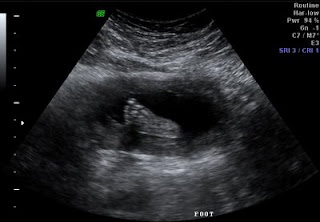

Finally here is a picture of the right foot. I love baby feet!